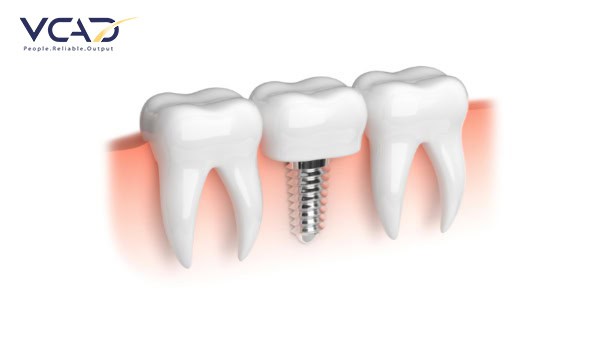

Cấy ghép răng là giải pháp thay thế răng tiên tiến mô phỏng cấu trúc toàn bộ của răng, từ chân răng đến thân răng. Chúng bao gồm ba thành phần chính:

- Phần Cấy Ghép (Implant Fixture): Đây là một trụ nhỏ, giống như vít thường làm từ titan tương thích sinh học. Nó được phẫu thuật cấy vào xương hàm, đóng vai trò là chân răng nhân tạo. Theo thời gian, xương sẽ gắn kết với phần cấy ghép qua một quá trình gọi là sự tích hợp xương (osseointegration), tạo ra nền tảng ổn định.

- Chân Răng (Abutment): Chân răng là một phần kết nối được gắn vào phần cấy ghép. Nó nhô lên trên đường viền nướu và đóng vai trò là cơ sở cho răng nhân tạo. Chân răng có thể được chế tạo theo yêu cầu hoặc chế tạo sẵn.

- Mão Răng (Dental Crown): Mão răng là phần nhìn thấy của cấy ghép, giống như một chiếc răng tự nhiên. Nó được chế tạo riêng để phù hợp với hình dạng, kích thước và màu sắc của các răng hiện có của bạn. Mão răng được gắn vào chân răng, hoàn tất việc phục hồi.